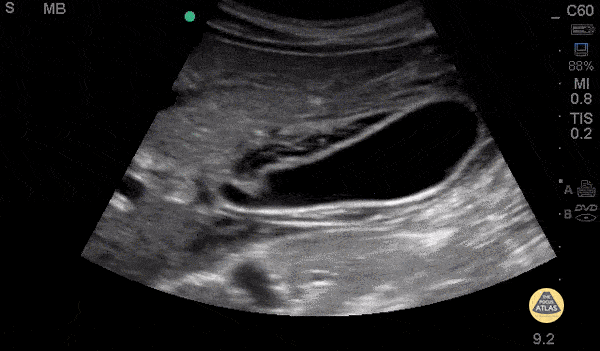

Biliary - Pericholecystic Fluid - Long

26 y/o F PMH HIV presents with non-bloody, non-bilious vomiting for one day associated with upper abdominal pain. POCUS revealed gallbladder wall thickening and pericholecystic fluid, but no gallstones or sonographic Murphy’s sign. The patient received symptomatic treatment and a surgical evaluation. The patient ultimately improved and was determined to not have cholecystitis. The patient was discharged home after her symptoms resolved and she was able to tolerate PO. Dr. Guru Shan, Dr. Guy Carmelli, Dr. Scott Kendal - Kings County Emergency Medicine